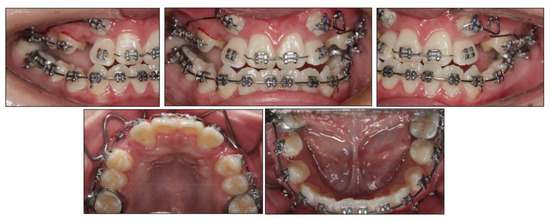

Figure 6. Presurgical facial and intraoral photographs.

2.4. Treatment Progress

Before the orthodontic treatment, the extraction of all retained deciduous teeth and maxillary first premolars were scheduled. After the extraction, both arches were bonded with preadjusted brackets (0.022-inch slot; 3M Unitek, Monrovia, CA, USA), aligned with initial 0.014-inch nickel titanium arch wires, and changed sequentially to eliminate crowding and provide leveling. Meanwhile, two impacted maxillary permanent canines were tracted through two auxiliary segmental 0.019 × 0.025-inch stainless steel arch wires with vertical helical loops (Figure 4). After 12 months, the canines were basically tracted into the right place. Presurgical decompensation started to increase the magnitude of surgical movement. The unfavorable tooth inclinations were corrected with 0.019 × 0.025-inch stainless steel arch wires through sliding mechanics to increase reverse overjet. A subepithelial connective tissue graft was also performed. Two connective tissue grafts were harvested from the palate and positioned in the prepared recipient site corresponding to the mandibular anterior region. The attached gingiva and keratinized tissue were augmented after the mucogingival surgery (Figure 5). After 34 months, the dentition preparation phase of presurgical treatment was completed in both arches (Figure 6).